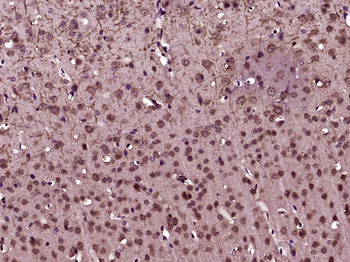

100 μl, 50 μl, 200 μl - ATF4 Recombinant Rabbit Monoclonal Antibody [orb704304]Featured

FC, ICC, IF, IHC-Fr, IHC-P, WB

Human

Mouse

Rabbit

Recombinant

Unconjugated

50 μl, 100 μl - MARK3 Recombinant Rabbit Monoclonal Antibody [orb704310]Featured